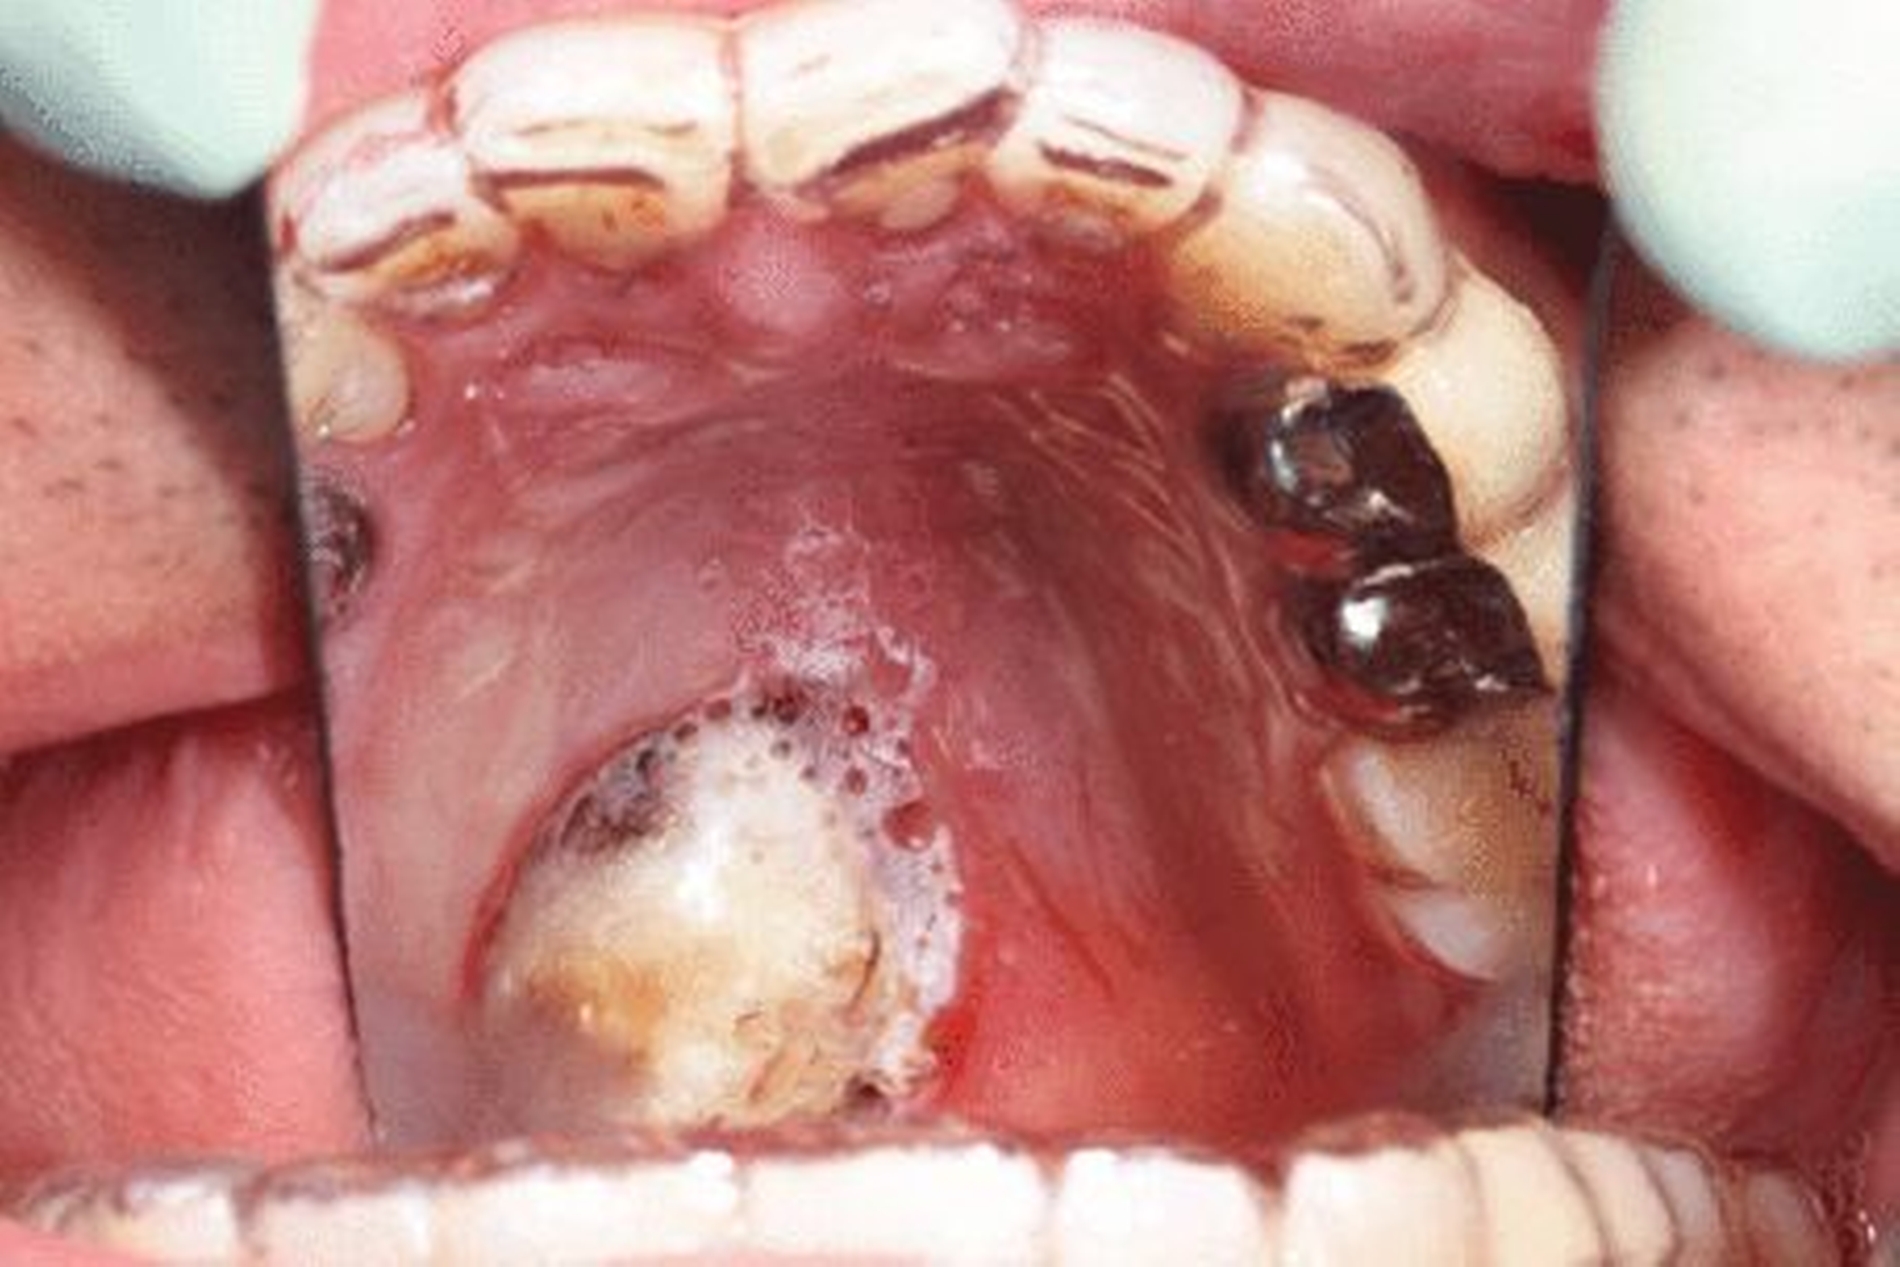

In der regelmäßigen Tumornachsorge beschrieb die Patientin zwei Jahre nach der Erstoperation eine neu aufgetretene persistierende Schwellung am anterioren Kieferstumpf. In der radiologischen Kontrolle mittels OPT stellten sich drei neue pathologische Befunde dar (Abbildung 2). Eine deutlich fortgeschrittene Osteolysezone am mesialen Kieferstumpf links, im Kinnbereich sowie im rechten Kieferwinkel. In der Computertomografie verdeutlichten sich drei Kontrastmittel aufnehmende, rundliche, glatt begrenzte Weichteilläsionen am Unterkiefer (Ausmaße paramedian: 17 mm, am aufsteigenden Ast rechts Regio 48: 18 mm x 17 mm, ehemaliges Operationsgebiet Regio 036: 15 mm x 24 mm). Im erneuten Staging ergab sich wie bei der Erstdiagnose kein Anhalt auf eine Fernmetastasierung.